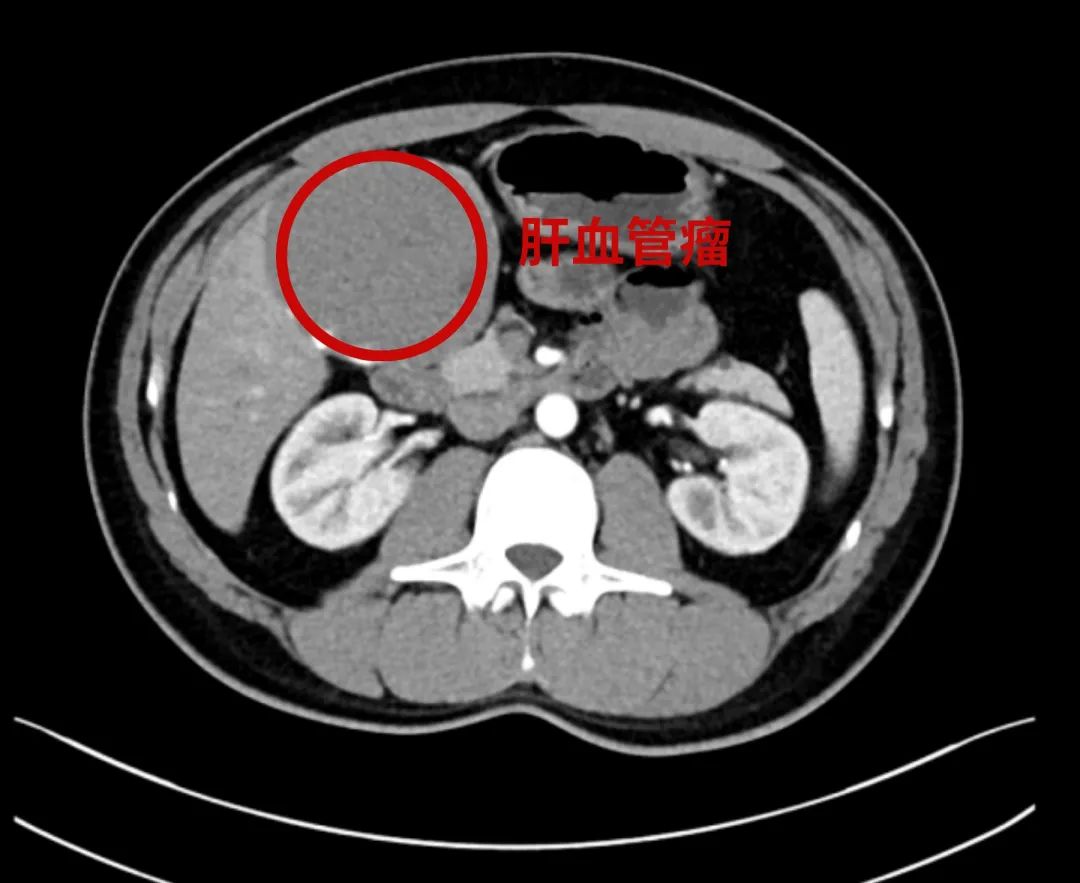

44岁的王先生8年前体检发现肝血管瘤,无不适症状,定期复查。一月前患者自觉右上腹胀痛不适,且右肋缘下可触及一包块,立即到昆山市一医院肝胆胰脾外科就诊,查增强CT提示肝血管瘤,直径达9cm,同时血管瘤内部合并局部出血。肝胆胰脾外科医生根据王先生的相关检查及临床症状,建议行腹腔镜下肝部分切除术,王先生表示同意。

增强CT可见肝血管瘤较大,且与胆囊紧密粘连

术中探查见肝脏Ⅳa、Ⅴ段脏面一肿块突出,大小约10×8×8cm,与胆囊浆膜融合,遂行腹腔镜下肝部分切除术,术中肝血管瘤包膜下完整切除,出血不到50ml。术后第一天王先生可下床活动,术后一周康复出院。